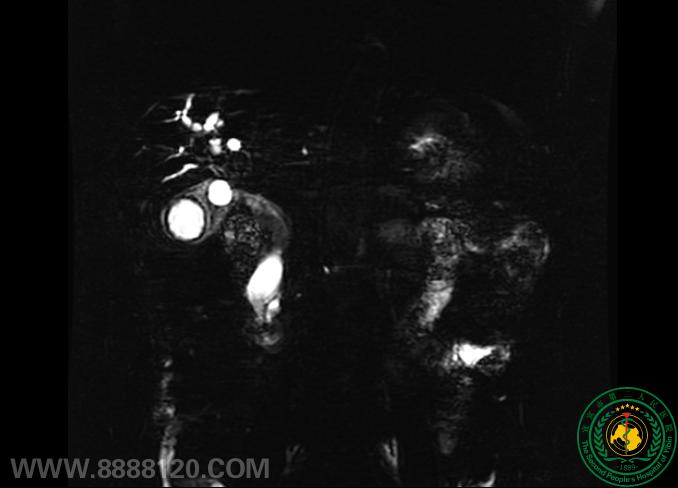

消化内镜医生的第三只眼----超声内镜

消化内镜医生的第三只眼----超声内镜54081